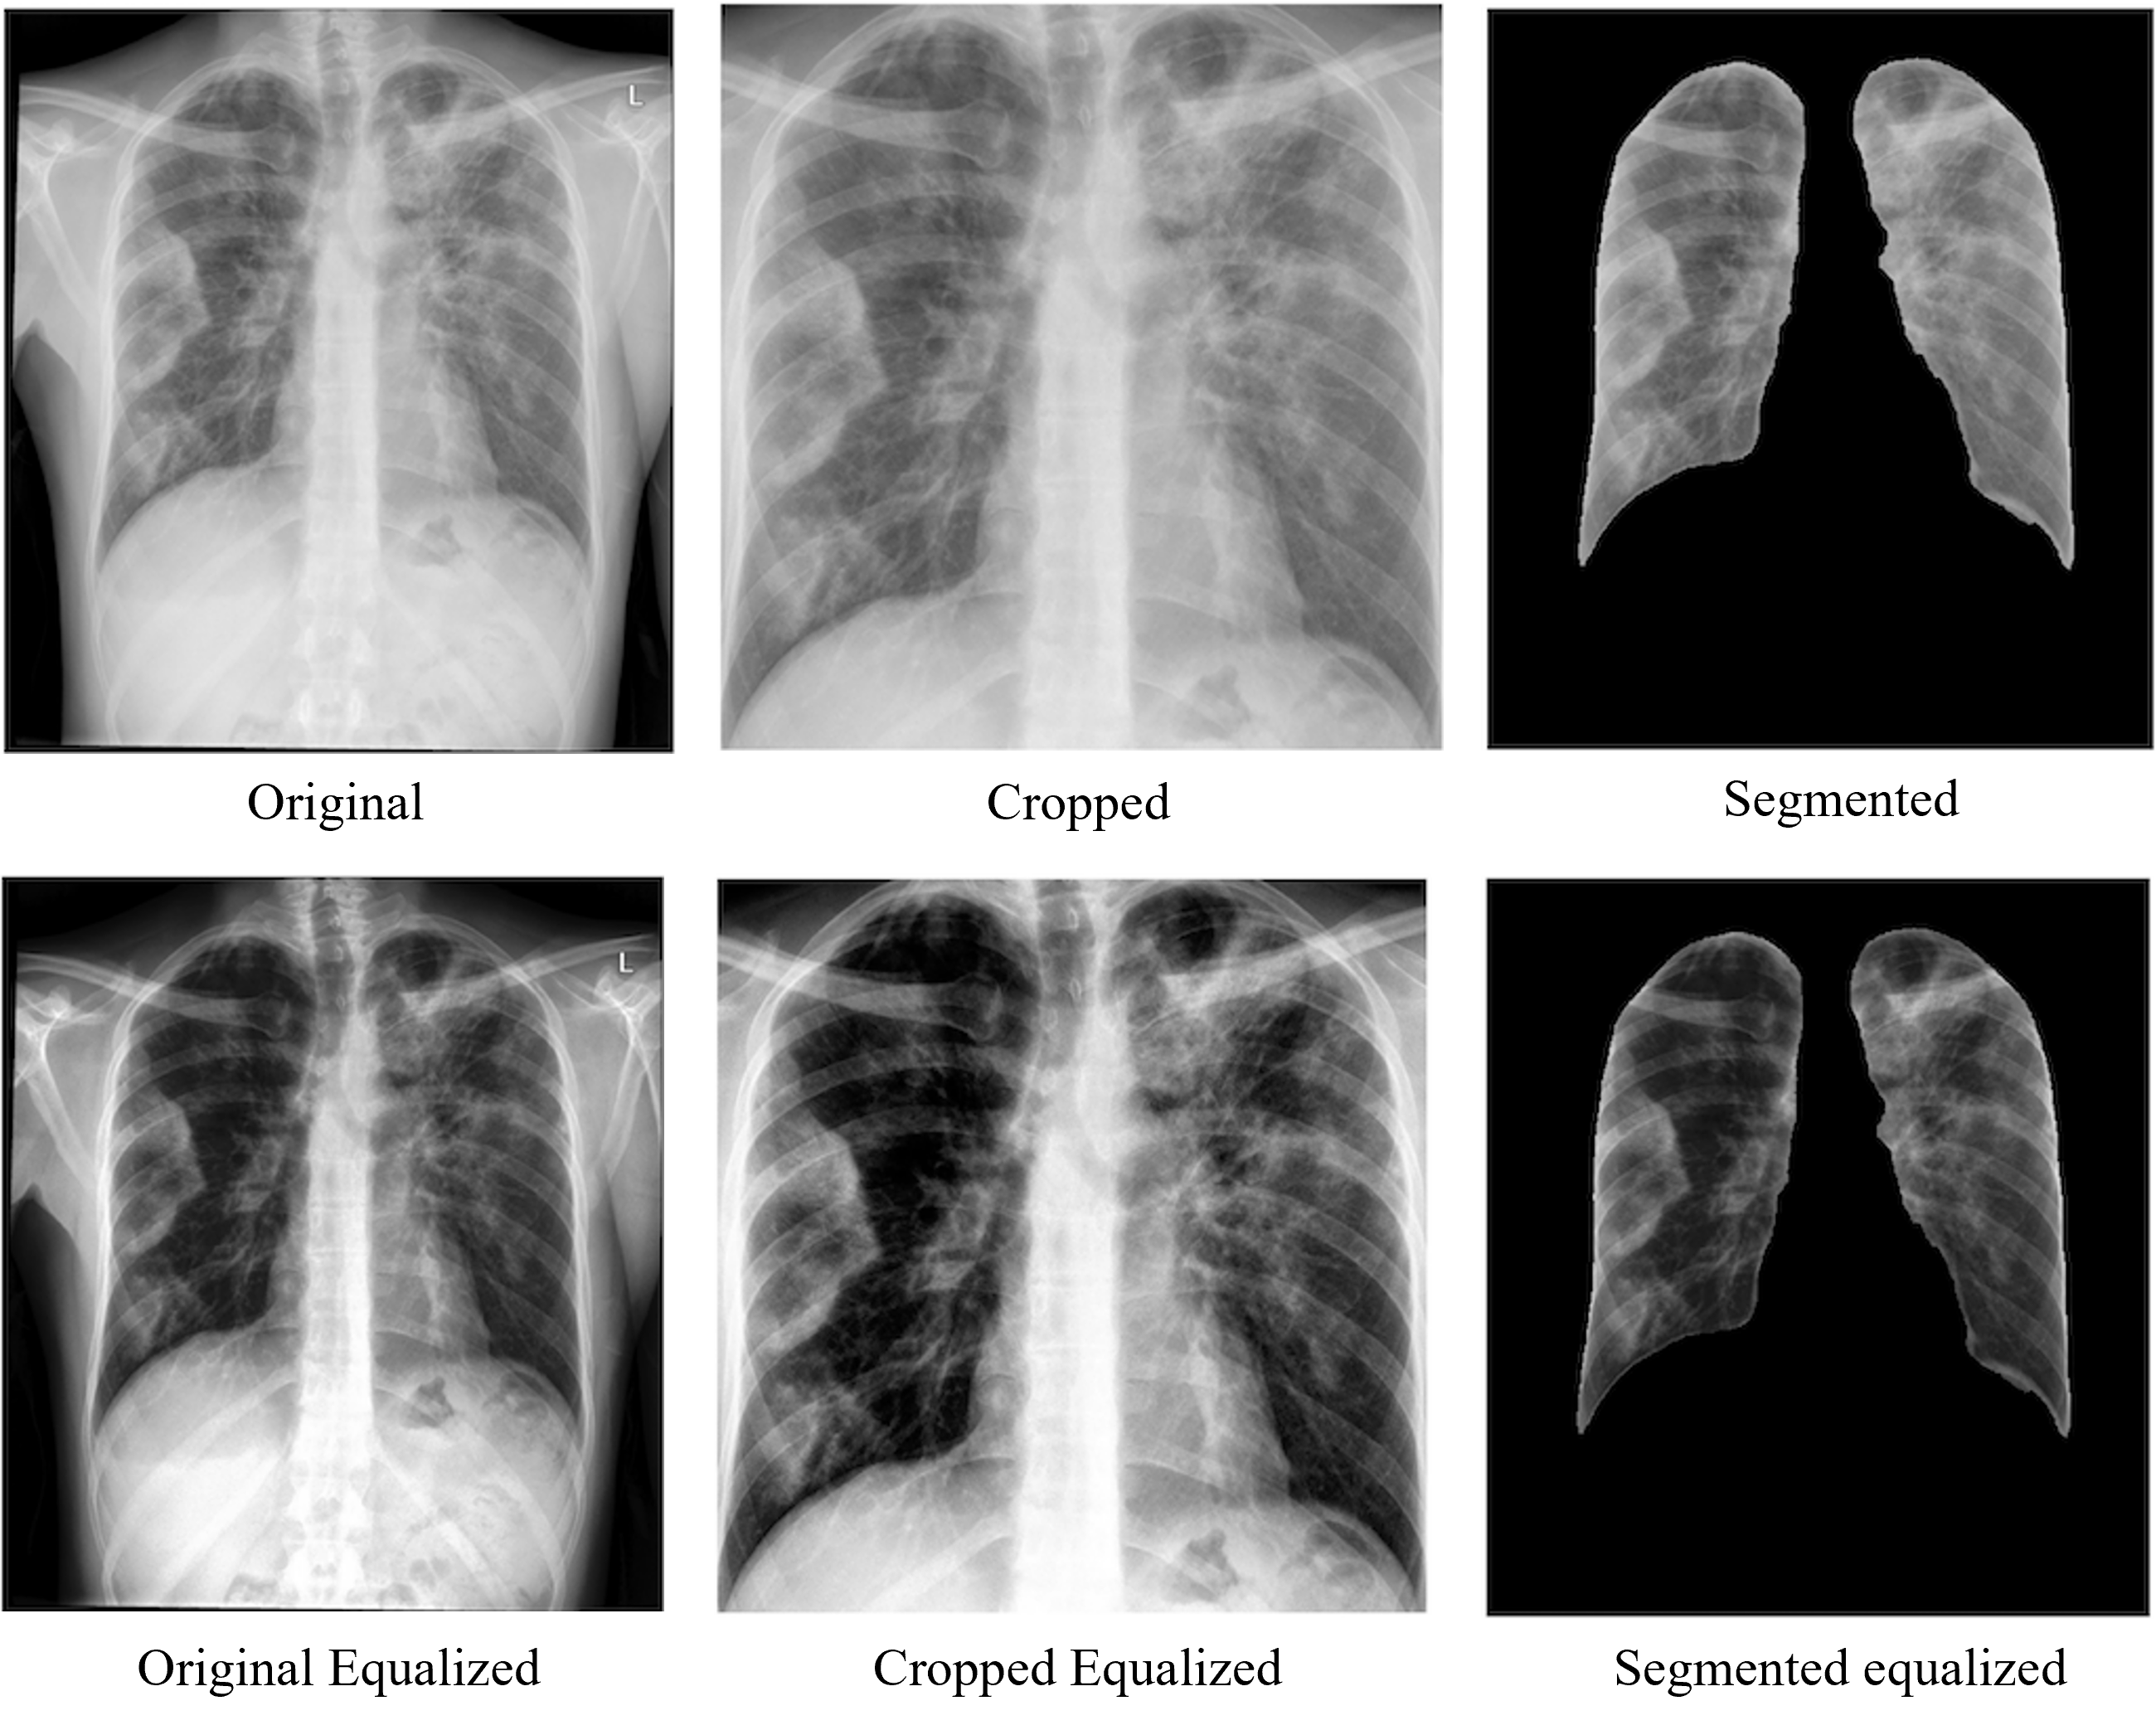

For experimental evaluation, we created our dataset by merging two COVID-19 X-ray image repositories: COVID-19 Posterior-Anterior Chest Radiography Images (X-rays) [140] and COVID-19 Radiography Database [141]. All images were resized to 224×224224224224\times 224224 × 224 to accommodate the input size of the deep learning foundation models. We applied various image preprocessing strategies (such as cropping, segmentation and histogram equalization) to assess their effects on the performance of a deep learning model. Figure 2 shows samples of different preprocessing techniques on COVID-19 chest X-ray images.

Figure 2: In addition to the original unaltered dataset, cropping and lung segmentation were used as preprocessing strategies. Another set of images was generated by individually applying histogram equalization to each preprocessing strategy.

Table 1 presents six versions of COVID-19 datasets created by applying various preprocessing strategies. Cropping was done by center-cropping the image to focus on the lung area [142], removing irrelevant parts such as arms, neck, shoulders, black surrounding areas and stomach areas, and then resizing the image to the model requirements. The dataset was segmented using a pre-trained ResNet34 model [143] with dice evaluation results of 0.9657. We used the X-ray segmentation library [143] to segment the left and right lungs by masking and cropping. Any other area without a lung was set to a pixel value of 0. The resulting image was the left and right lungs on a black background. The same image test data set has been used consistently across the foundation model testing and continual learning testing.